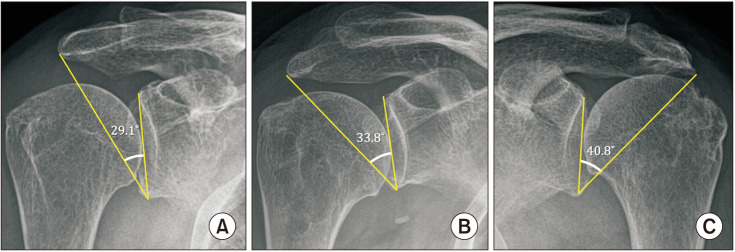

背景:临界肩角(CSA)是一项重要的放射学测量,与三角肌和肩袖生物力学密切相关。我们假设CSA影响逆行全肩关节置换术(RTSA)前后肩关节的生物力学。方法:156例肩胛内侧/肱骨外侧设计行RTSA的患者,根据术前CSA情况分为低CSA组(< 30°)、中CSA组(30°-35°)、高CSA组(> 35°)。通过x线及ct测量三组患者术前、术后肱骨外侧偏移量(LHO)、肩肱距离(AHD)、术后三角肌包裹角(DWA)、三角肌力臂(DMA),并进行比较。比较三组患者在休息和运动时疼痛评分、美国肩关节外科医生评分、加州大学洛杉矶分校肩关节评分和Constant肩关节评分的改善情况。结果:低CSA组术后LHO最大(16.62±4.76 mm),高CSA组术后LHO最小(13.68±5.59 mm, p = 0.03)。术后AHD以低CSA组最高(28.72±5.42 mm),高CSA组最低(25.21±5.12 mm) (p = 0.004)。两组术后DWA、DMA及临床评分改善无显著差异(p < 0.05)。术后发生肩峰骨折5例(3.2%),其中中度CSA组1例,高CSA组4例。结论:低CSA患者肱骨侧化设计的RTSA比中CSA或高CSA患者的肱骨侧化和远端化更多,尽管差异小于5mm。与三角肌活动相关的影像学和术后临床结果的改善,如活动范围、DWA和DMA,在不同csa患者之间没有显著差异。因此,在RTSA期间,CSA对肱骨成分的选择没有帮助,因为基于CSA的临床或功能结果没有显着差异。

Methods: One hundred and fifty-six patients (156 shoulders) who underwent RTSA with medial glenoid/lateral humerus design were divided into 3 groups according to preoperative CSA: low CSA group (< 30°), intermediate CSA group (30°-35°), and high CSA group (> 35°). The preoperative and postoperative lateral humeral offset (LHO) and acromiohumeral distance (AHD) and postoperative deltoid wrapping angle (DWA) and deltoid moment arm (DMA) were measured on x-ray and computed tomography and compared between the 3 groups. The improvement of the pain score, assessed using the visual analog scale at rest and motion, American Shoulder and Elbow Surgeons score, University of California, Los Angeles shoulder score, and Constant shoulder score were compared between the 3 groups.